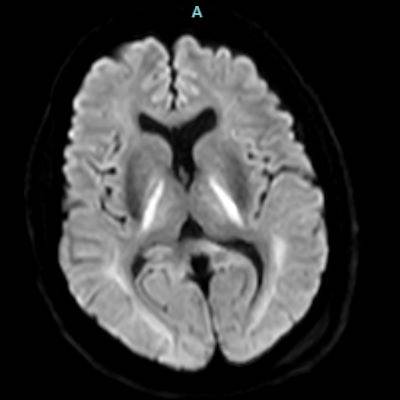

66 yaş, E

Kardiak arrest, 10 dk CPR öyküsü